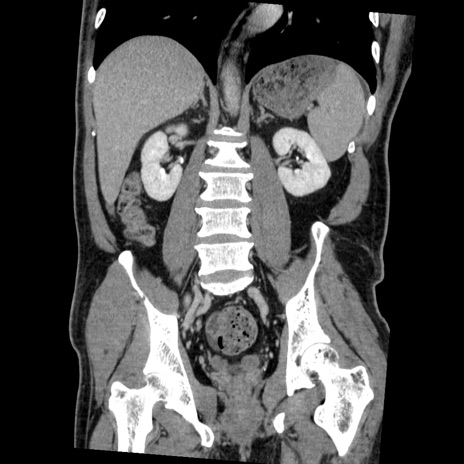

症例22(冠状断像)

【症例】50歳代男性

【主訴】腹痛

【現病歴】AVMからの被殻出血のため回復期リハ病棟入院中。 本日午後3時頃急に下腹部痛が出現した。

【既往歴】AVM、被殻出血、虫垂炎、高血圧

【身体所見】意識晴明、左半身不全麻痺、会話の理解は良好、36.5°C、腹部:膨隆、全体に板状硬、下腹部正中に圧痛点あり、反跳痛-、筋性防御不明、右下腹部にope scar

【データ】WBC 9400、CRP 0.06